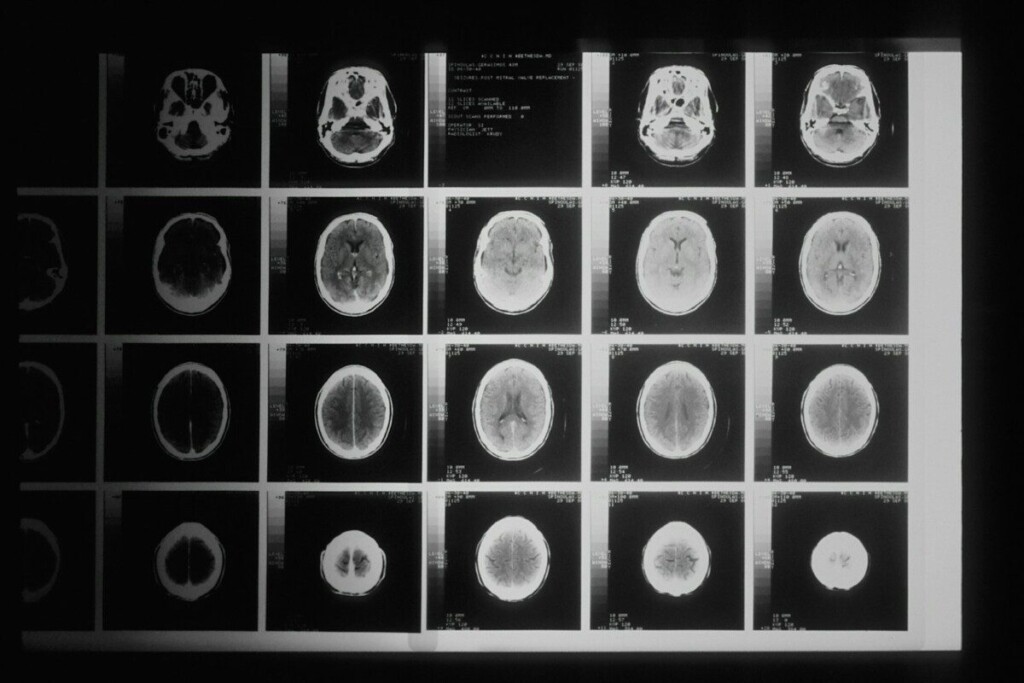

Jogailos universiteto (Lenkija) mokslininkai kuria naują, gerokai saugesnį vaistų pristatymo į smegenis būdą. Jų sukurta technologija leidžia cheminių preparatų dozes nukreipti tiesiai į naviką arba į smegenis per nosies ertmę. Taip mažinamas bendras toksinis poveikis organizmui ir atsiveria perspektyvos veiksmingesniam smegenų vėžio gydymui.

Sukurtas preparatas gali būti vartojamas ir per nosį, gelinio aerozolio pavidalu. Tokiu atveju vaistas smegenis pasiekia per uoslės ir trišakio nervo galūnes, apeidamas kraujo–smegenų barjerą, kuris ilgą laiką buvo viena didžiausių kliūčių gydant centrinės nervų sistemos navikus.